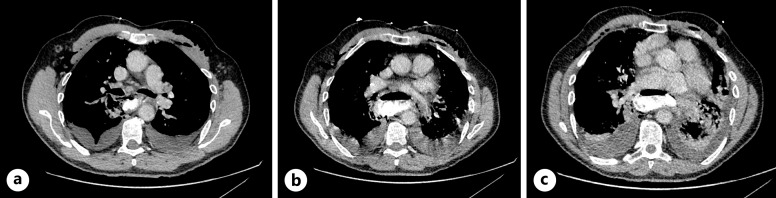

简介布尔哈韦综合征是一种罕见的疾病,发病率和死亡率都很高。及时干预可大大改善预后,手术是传统的主要治疗方法。最近,治疗性内窥镜技术的进步使人们对腔内真空疗法(EVT)越来越感兴趣,这是一种微创技术,可以对伤口进行清创和引流,促进肉芽组织的形成。EVT 具有积极的临床效果,包括与手术和支架治疗吻合口漏相比死亡率较低,其次是食道穿孔。EVT在欧洲已被广泛采用,但在英国却鲜有报道:我们报告了三例 Boerhaave 综合征病例,这些病例均使用 Eso-SPONGE ®(B.Braun Medical Ltd,英国谢菲尔德)EVT 成功治愈。EVT包括将聚氨酯海绵放入伤口腔内。首先对创腔进行评估,然后通过导管插入海绵,最后拔出导管。确认海绵位置,必要时进行调整。海绵通过经鼻引流管连接到持续负压吸引器,每 3-5 天更换一次。由于被认为不适合手术,所有 3 名患者都被转诊接受了 EVT。所有患者均恢复良好,并已出院回家:结论:对于不适合手术的波尔哈韦综合征患者,EVT 是一种有效的治疗策略。使用 Eso-SPONGE 有助于引流化脓灶和闭合缺损,使患者完全康复。我们的研究结果支持现有的证据,即 EVT 是治疗 Boerhaave 综合征的一种很有前景的方法。

Case presentations: We report three cases of Boerhaave syndrome, successfully managed with EVT, using the Eso-SPONGE ® (B.Braun Medical Ltd, Sheffield, UK). EVT involves the placement of a polyurethane sponge into the wound cavity. The cavity is initially assessed, then an overtube is introduced through which the sponge is inserted, and then the overtube is removed. Sponge position is confirmed and adjusted if necessary. The sponge is connected via a trans-nasal drain to continuous negative pressure suction and is changed every 3-5 days. Having been deemed surgically unfit, all 3 patients were referred for EVT. All patients made excellent recovery and were discharged home.